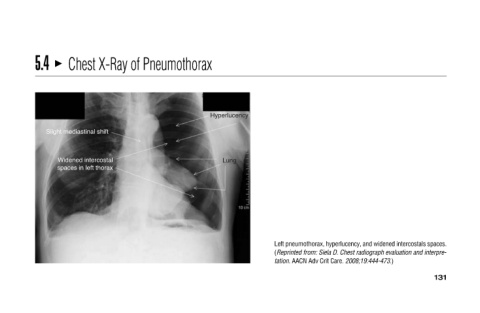

Left pneumothorax, hyperlucency, and widened intercostals spaces.

tation. AACN Adv Crit Care. 2008;19:444-473.) (Reprinted from: Siela D. Chest radiograph evaluation and interpre-

Hyperlucency Lung

Chest X-Ray of Pneumothorax

Slight mediastinal shift Widened intercostal spaces in left thorax